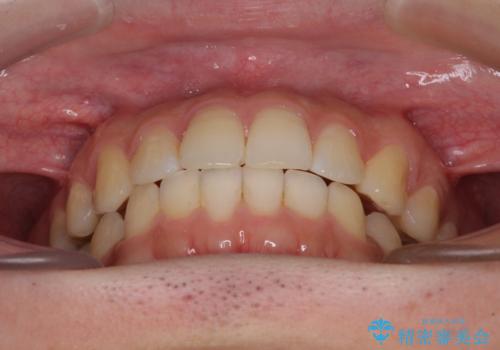

インビザライン・ライトによる矯正治療の後戻り改善

- 矯正治療の後戻りを気にして来院された患者様です。

後戻りは軽微でしたので、インビザライン・ライトにより矯正治療を行うこととしました。

再矯正後の後戻りを防ぐため、歯列排列後に、下顎前歯はワイヤーによる固定を行いました。

下顎前歯の歯列を動かないようにしておくことで、上顎前歯の後戻り防止にも効果を発揮します。